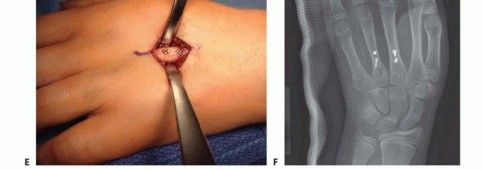

Once reduced, fixation can be achieved via crossed Kirschner wires or retrograde intramedullary pinning (the "bouquet" technique). However, the modern gold standard for minimally invasive fixation is the retrograde intramedullary headless compression screw. A small stab incision is made over the dorsal aspect of the flexed MCP joint. The entry portal is meticulously established in the articular "safe zone" of the metacarpal head—specifically the dorsal-ulnar or dorsal-radial collateral recess, strictly avoiding the central weight-bearing articular cartilage.

A guidewire is advanced down the medullary canal across the fracture site under fluoroscopic guidance. After confirming perfect rotational alignment and length, the canal is sequentially broached or drilled, and an appropriately sized headless compression screw is buried beneath the articular cartilage. This technique provides robust, load-sharing stability that allows for immediate, unrestricted active range of motion, vastly reducing the incidence of postoperative stiffness compared to traditional K-wire constructs.

Open Reduction and Internal Fixation (ORIF) Approaches

When closed reduction fails, or for complex, comminuted, or multiple metacarpal fractures, Open Reduction and Internal Fixation (ORIF) is mandated. A dorsal longitudinal or slightly gently curved incision is made centered over the fractured metacarpal. Careful subcutaneous dissection is performed to identify and meticulously retract the dorsal sensory nerve branches using vessel loops. The extensor apparatus is exposed. Depending on the fracture location, the extensor tendon can be retracted laterally, or the extensor mechanism can be split longitudinally (e.g., splitting the EDC tendon) to access the dorsal periosteum.

Following definitive fixation, a rigorous fluoroscopic check is performed in multiple planes to confirm anatomical reduction, appropriate hardware placement, and crucially, to ensure no screws are penetrating the volar cortex excessively, which could tether the underlying flexor tendons. The tourniquet is deflated, meticulous hemostasis is achieved, and the extensor mechanism is meticulously repaired with fine absorbable sutures. The skin is closed without tension, and a bulky, well-padded dressing is applied, splinting the hand in the intrinsic-plus position.

Clinical & Radiographic Imaging Archive